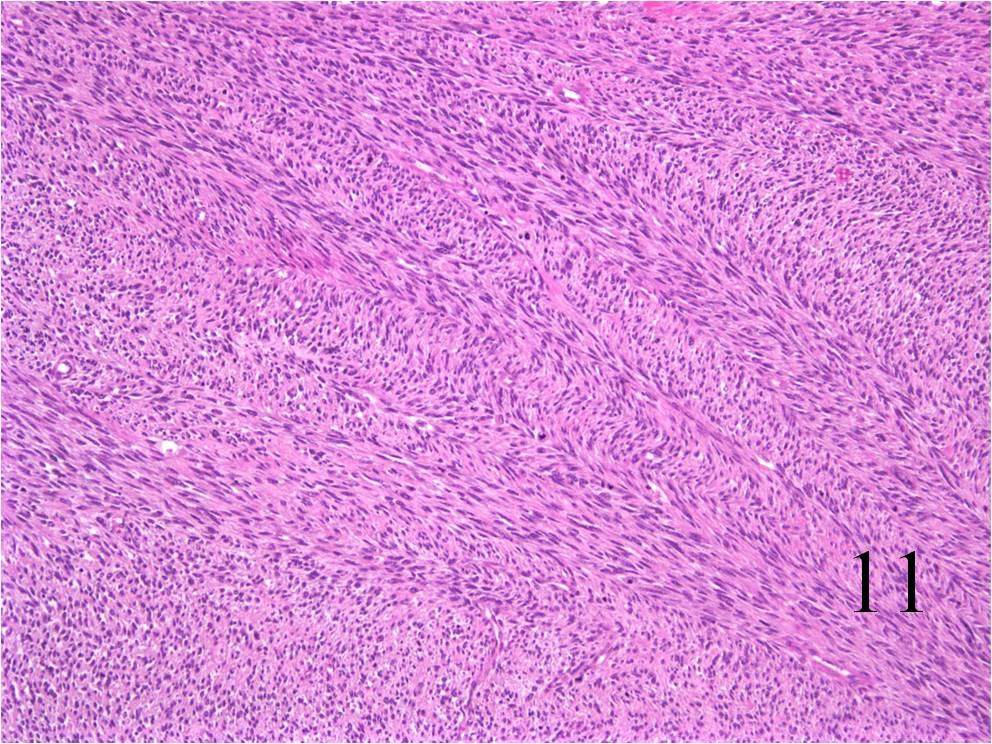

Microscopic

- Embryonal:

- Small round blue cells (Fig. 12-15)

- Round, oval, polygonal cells

- Fibrotic/myxoid stroma

- Rhabdomyoblast: well differentiated will have cross striations

- Pleomorphic:

- Essentially identical to pleomorphic MFH

- Admixture of spindle-shaped, pleomorphic polygonal, round cells

- Arranged in fascicular, storiform, and patternless pattern

- Nuclei is large, oval-round, and multiple.